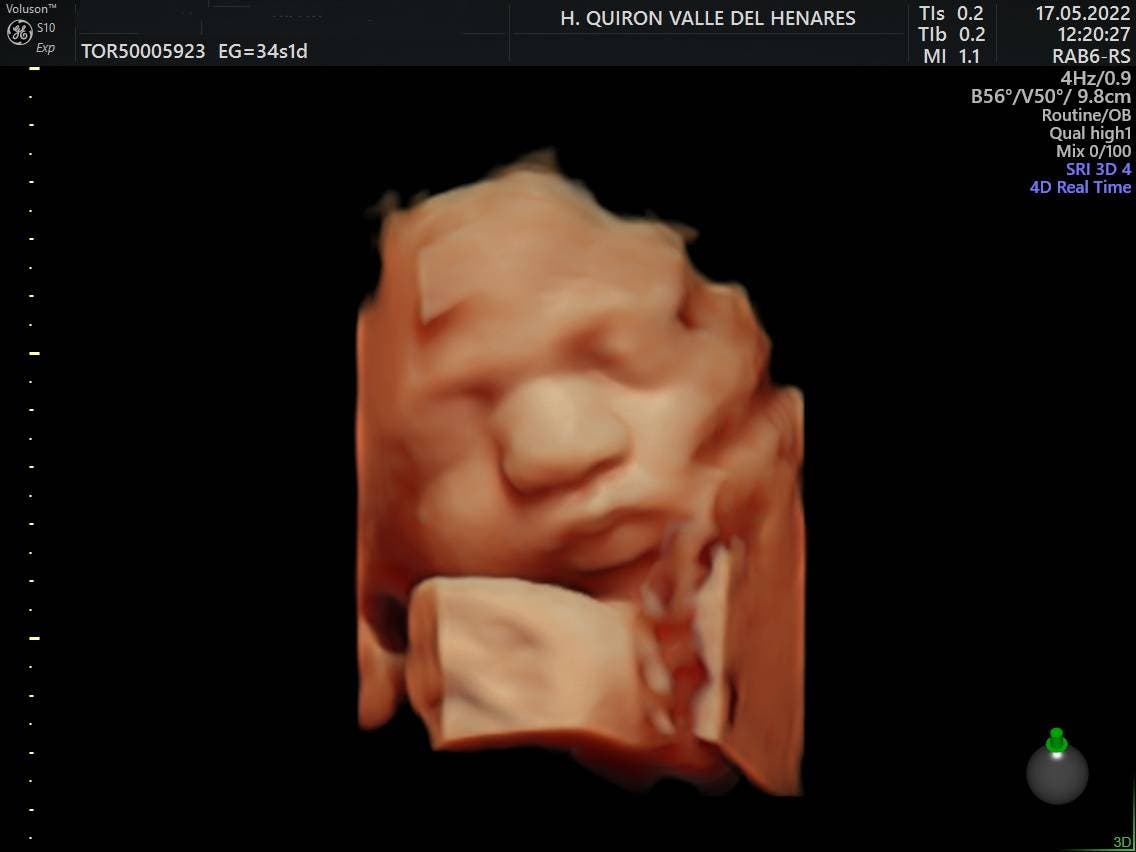

El Hospital Quirónsalud Valle del Henares incorpora un nuevo ecógrafo con tecnología 5D

Este tipo de ecografías permiten a los progenitores obtener imágenes muy realistas de su bebé, además de valorar el estado de bienestar del mismo.

El Hospital Quirónsalud Valle del Henares, en Torrejón de Ardoz, ofrece la posibilidad de realizar ecografías gestacionales 5D. Este tipo de exploración permite obtener una imagen muy realista del bebé y se puede realizar en cualquier etapa de la gestación -aunque lo recomendado es realizarla entre las semanas 28 y 32 de gestación, ya que técnicamente es el mejor momento y es mucho más probable obtener imágenes de buena calidad-.

Al final de la prueba, se entrega a la familia un informe de la ecografía y un soporte digital que contiene las imágenes y los vídeos realizados.  Las ecografías 4D y 5D son también llamadas emocionales por la explosión de sensaciones que genera cuando la madre ve por primera vez la imagen del bebé que espera.

«Realizar esta ecografía con nuestro equipo de diagnóstico prenatal tiene un valor añadido», señala la Dra. Rocío Vellido Cotelo, Jefa Asociada de Ginecología y Obstetricia del Hospital Quirónsalud Valle del Henares, «dado que quien realiza la prueba es un especialista en la materia, siempre se completa la exploración con un examen morfológico y de perfil biofísico fetal, que permita valorar el estado de bienestar del bebé más allá de la captura de vídeos y fotografías».